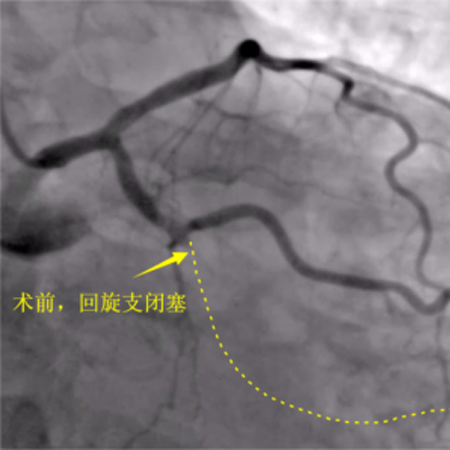

造影可见:前降支中段发出对角支后极重度狭窄,可见侧支循环右冠中远端,回旋支发出钝缘支后闭塞,可见钝缘支侧支循环回旋支远端;右冠中段闭塞。

在家修养一段时间后,老吴再次来到了我科,要求把最后闭塞的回旋支开通。虽然我和老吴已经建立了很好的医患信任关系,但我还是不得不给他泼一桶冷水,这次的回旋支闭塞,不知道闭塞了多久,也就是我们称呼的CTO,我也不能保证能开通。

CTO患者的冠脉闭塞时间较长,斑块往往坚硬,或伴有钙化,手术导丝难以顺利通过,且很多闭塞段后续没有明确的血管走行方向,导丝就容易穿过血管内膜甚至穿透血管,所以CTO病变行经皮冠状动脉介入治疗(PCI)的手术难度大、操作时间长、成功率低,因而CTO病变被认为是冠脉介入治疗的‘最后堡垒’。

12月3日,老吴第三次进入导管室,这次老吴很轻松,和我还有说有笑,而我却承受了比上次更大的压力,因为老吴是带着肯定而来,带着信任而来。结果左侧造影回旋支远端的同侧逆向供应血流消失了,不得不穿刺左手进行右冠造影为左冠回旋支导丝前进提供方向,皇天不负有心人,经过重重困难最终再次顺利开通了闭塞的回旋支,这一刻如释重负,汗水打湿了衣物,浸透了铅衣!